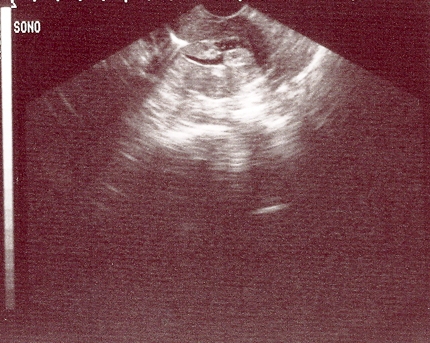

Sonohysterography demonstrates a posterior submucous uterine fibroid deforming the posterior endometrial cavity

From the personal collection of Dr M.F. Mitwally and Dr R.J. Fischer; used with permission